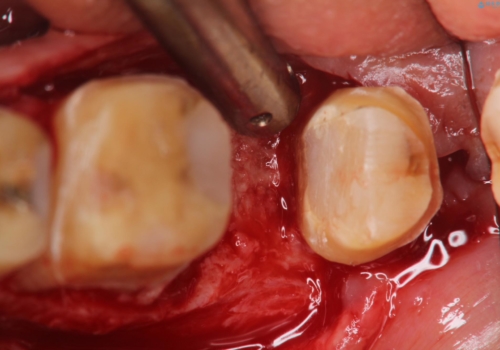

近心根が垂直破折しており保存不可能で抜歯適応だと判断しましたが、できることなら少しでも保存したいとの希望があり、今後のリスクを説明した上で遠心根を保存する意思決定を行いました。

条件が少しでもよくなる様に、再生治療および確定外科を行い良好な歯周状態でオールセラミッククラウンを装着しております。